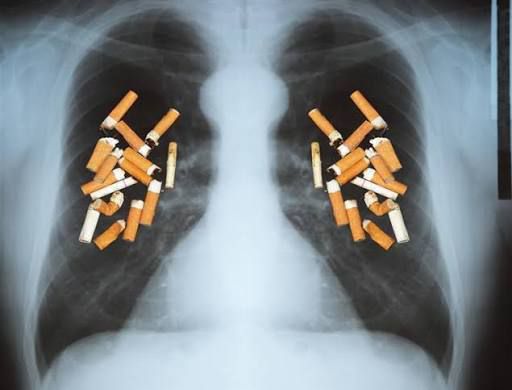

الدكتور الطراونة يوضح ..المدخن بلا أعراض ليس معافى بل يفقد نصف رئة قبل أن يشعر بأول ضيق تنفس.

أكد استشاري الأمراض الصدرية ، الدكتور محمد حسن الطراونة، أن غياب الأعراض لدى المدخن لا يعني إطلاقاً سلامة الرئتين، واصفاً حالة المدخن “المستقر” بأنها حالة “تعويض مؤقت” وليست حالة صحية، حيث تعتمد الرئة على احتياطي وظيفي هائل يخفي وراءه دماراً صامتاً.

وأوضح الدكتور الطراونة أن الرئة البشرية تمتلك “احتياطياً وظيفياً” كبيراً يسمح للإنسان بفقدان ما يصل إلى 50% من مساحة الحويصلات الهوائية دون الشعور بضيق التنفس أثناء الأنشطة اليومية. وقال: “إن غياب الأعراض هو في الحقيقة وجود لهذا الاحتياطي، وعندما يبدأ المريض بالشعور بالنهجان عند صعود الدرج، فهذا يعني طبياً أن (الإفلاس) قد وقع بالفعل، وأن نصف الرئة قد خرج عن الخدمة نهائياً”.

وكشف الطراونة عن وجود ما يسمى بـ “المنطقة الصامتة” في الجهاز التنفسي، وهي القصبات الهوائية الدقيقة (أصغر من 2 ملم)، مؤكداً أن الفحوصات التقليدية مثل فحص كفاءة الرئة (FEV1) قد تكون مضللة.

وشبّه الطراونة الأمر بقوله: “التدخين يقتل الرئة كالشجرة التي تموت من أوراقها (الأجزاء الدقيقة) باتجاه الجذع، بينما نحن نكتفي بقياس سماكة الجذع فقط. لذا يظل فحص التنفس طبيعياً لسنوات بينما تكون الأجزاء الحيوية في حالة اندثار”.

ودعا الطراونة الأطباء والمدخنين للتركيز على مؤشرات أدق مثل (DLCO) لقياس قدرة تبادل الغازات، وفحص (FEF 25-75%) الذي يكشف تضرر القصبات الصغيرة قبل سنوات من انهيار الوظائف الكبرى.

وفي تشريح علمي دقيق، أشار الطراونة إلى أن سيجارة واحدة كفيلة بشل عمل “الأهداب التنفسية” التي تعمل كعمال نظافة للرئة لعدة ساعات. وأضاف: “المدخن الذي يستهلك علبة يومياً يعاني من شلل مستمر في آلية التنظيف الذاتي، مما يؤدي لتراكم المواد المسرطنة وتجنيد الخلايا الالتهابية (Neutrophils) التي تفرز إنزيماً يهضم نسيج الرئة حرفياً، وهو ما يحدث يومياً وبصمت دون حتى الحاجة لوجود سعال”.

وحذر الطراونة من الركون إلى نتائج الأشعة السينية (X-ray) العادية، مؤكداً أنها لا تظهر التوسع الرئوي أو “الإمفيزيما” إلا بعد دمار 30% من الرئة. ونصح بإجراء الصور الطبقية المقطعية بجرعات منخفضة (Low-Dose CT) لمن يرغب في رؤية الحقيقة، فهي الوحيدة القادرة على كشف “الثقوب” والدمار المبكر في نسيج الرئة.

واختتم الدكتور محمد حسن الطراونة تصريحه برسالة مباشرة لكل مدخن

أنت تملك حساباً بنكياً من الأكسجين، والتدخين هو سحب يومي من هذا الرصيد. الآن تشعر بأنك (غني) لأنك لا تشعر بضيق التنفس، لكنك تستنزف مدخراتك. التوقف الآن يعني الحفاظ على ما تبقى من رصيدك، أما الانتظار حتى تظهر الأعراض، فهو يعني أنك ستقضي بقية حياتك تحاول النجاة، لا العيش